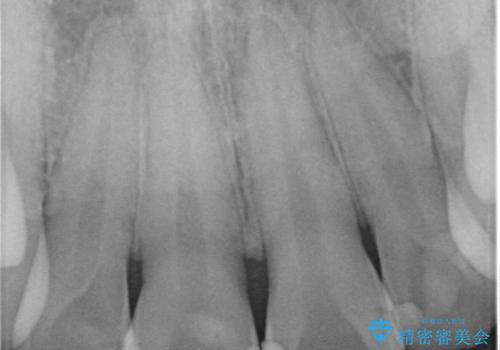

- 前歯を綺麗にしたいとの事で来院。

まずは仮歯を発注して仮歯にして最終的な被せ物の形を整えてジルコニアクラウンstで処置を行いました。